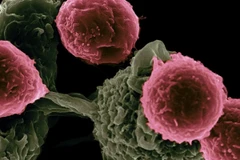

Lần đầu tiên một quả thận của lợn được cấy ghép trên cơ thể người mà không bị hệ thống miễn dịch đào thải ngay lập tức, mở ra triển vọng có thể giúp giảm sự thiếu hụt nghiêm trọng các cơ quan nội tạng phục vụ cấy ghép trên người.

Thử nghiệm trên được Trung tâm Y tế NYU Langone ở thành phố New York, Mỹ, tiến hành bằng việc sử dụng thận của một con lợn đã được biến đổi gene để các mô của nó không chứa các phân tử gây kích hoạt sự đào thải ngay lập tức của hệ thống miễn dịch con người.

Trong hàng chục năm qua, các nhà khoa học đã tiến hành nghiên cứu thử nghiệm khả năng sử dụng nội tạng động vật để cấy ghép cho người nhưng gặp cản trở khi xuất hiện sự đào thải ngay lập tức của cơ thể con người.